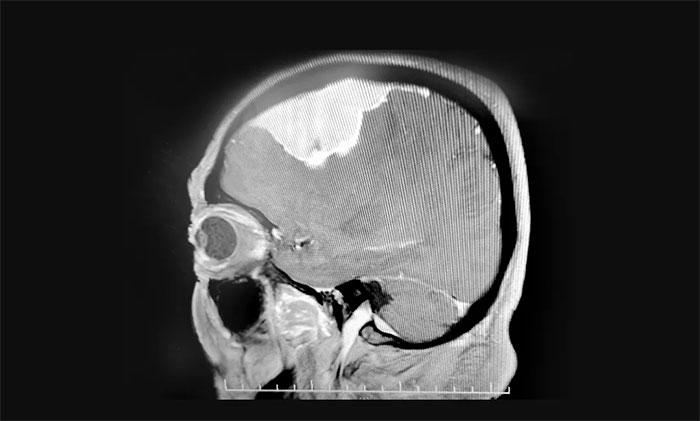

入院檢查,頭顱MRI提示:左側(cè)額葉大腦凸面可見巨大團(tuán)塊狀異常信號(hào),周圍可見明顯水腫信號(hào),胼胝體明顯腫脹,臨近左側(cè)腦室受壓向右側(cè)移位,中線結(jié)構(gòu)輕度右移,病灶大小約7.2×3.3×3.2cm。

▲ 腫瘤位于左側(cè)額部